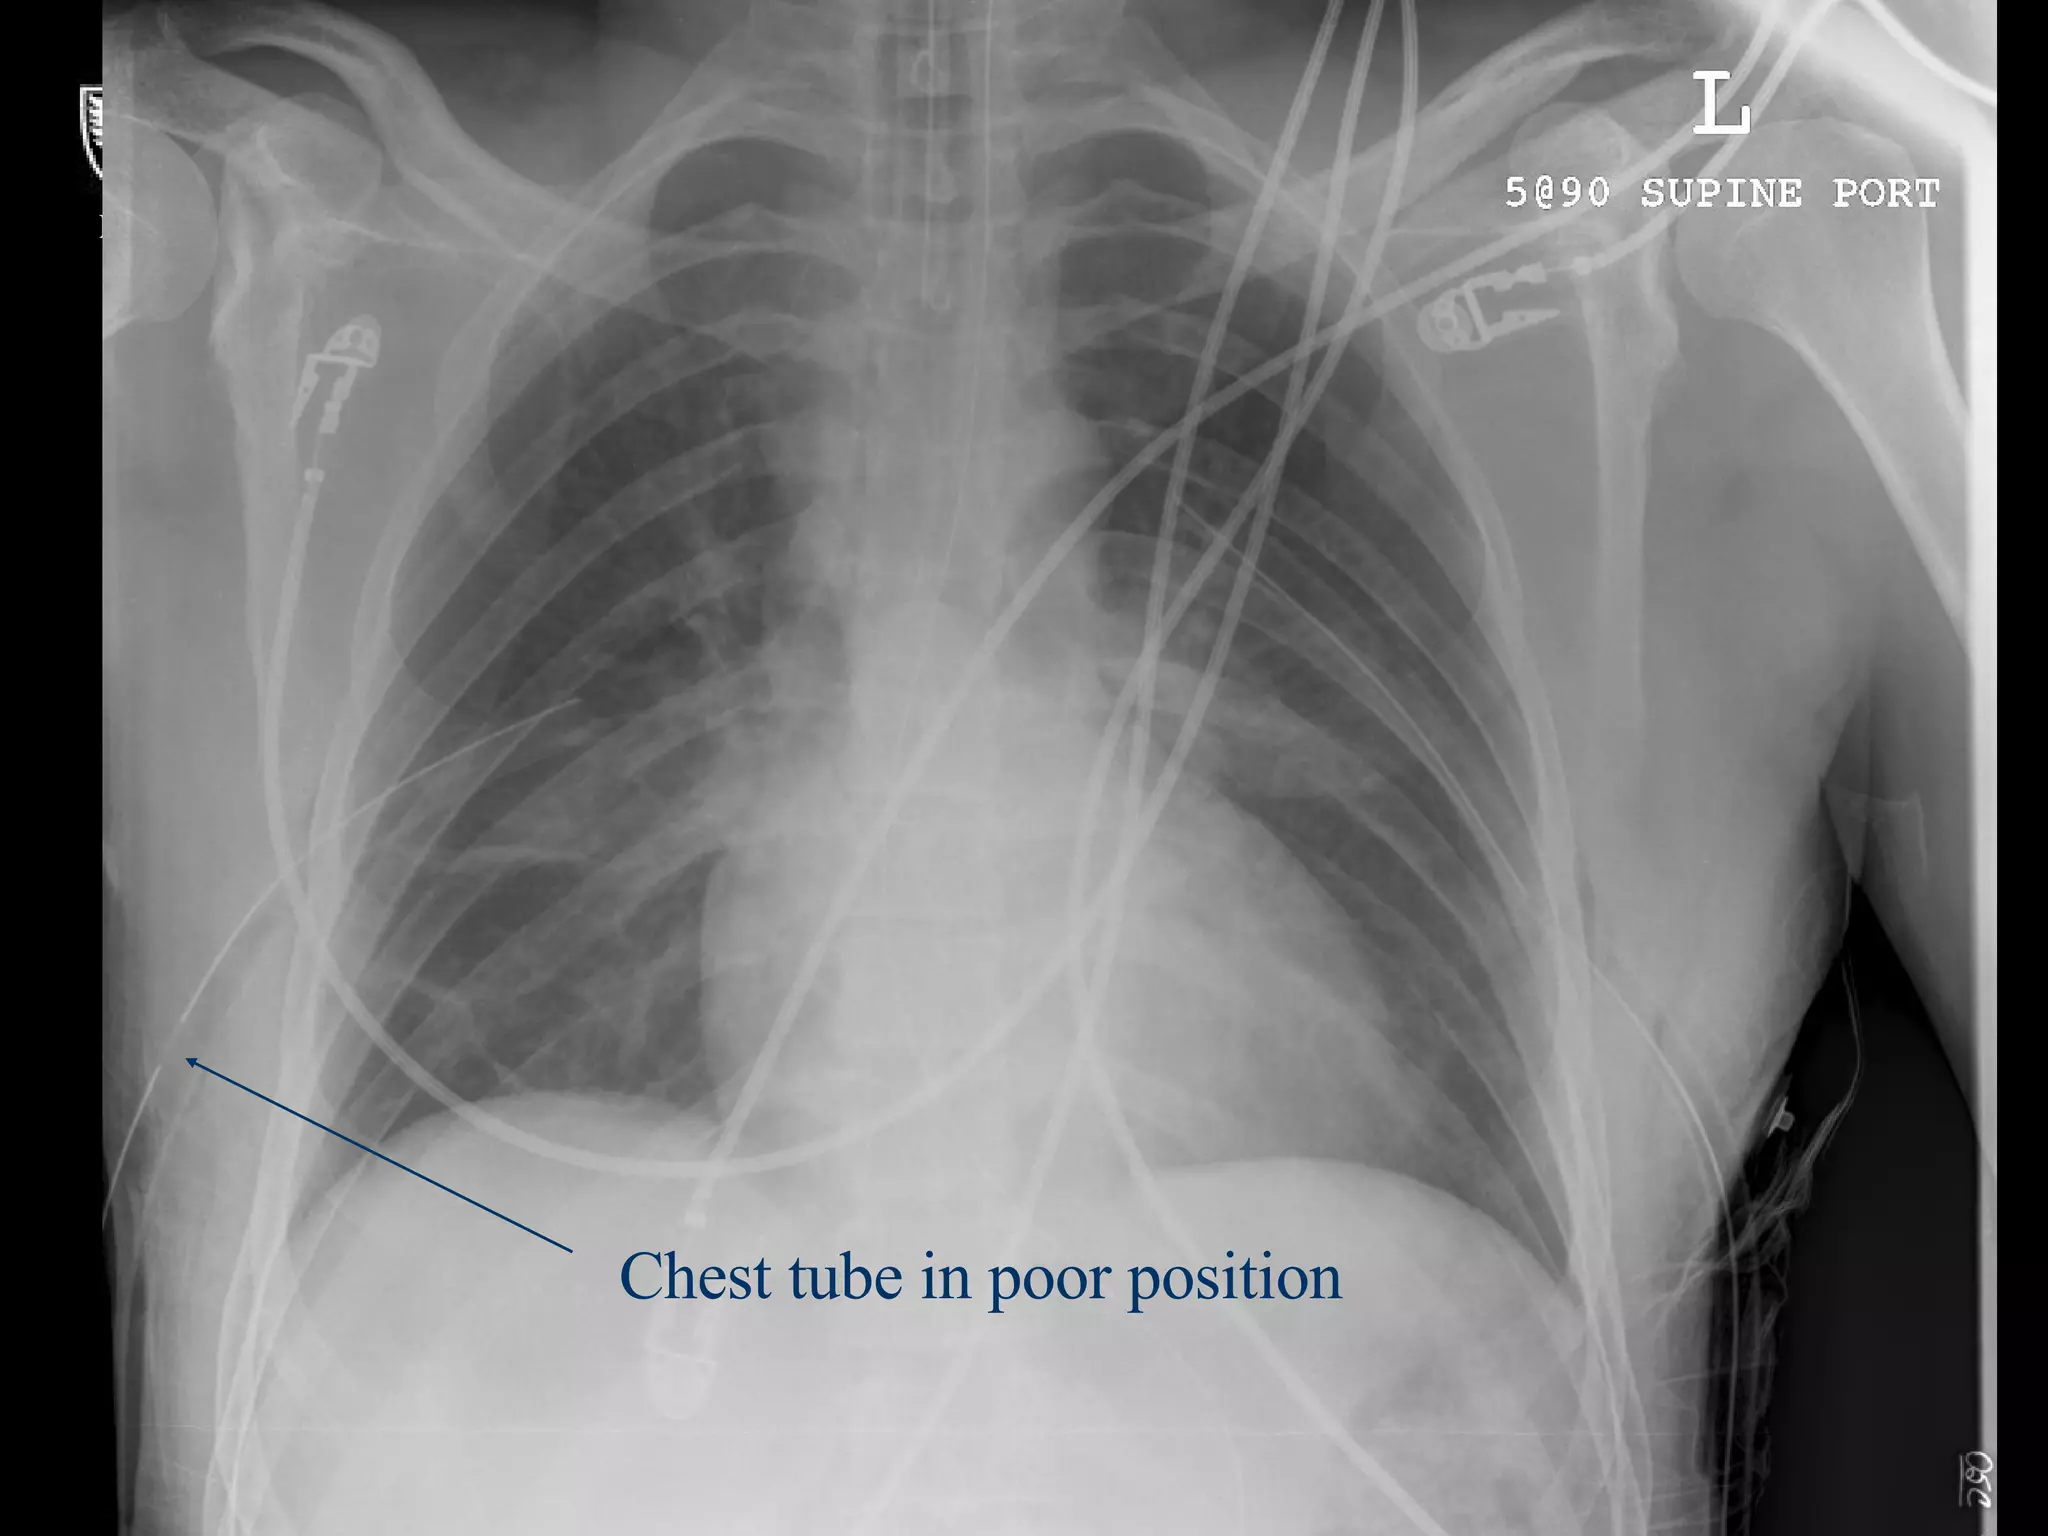

What’s Wrong With These Pictures?

Chest tube in poor position

What’s Wrong WithThese Pictures?

Chest tube inpoor position